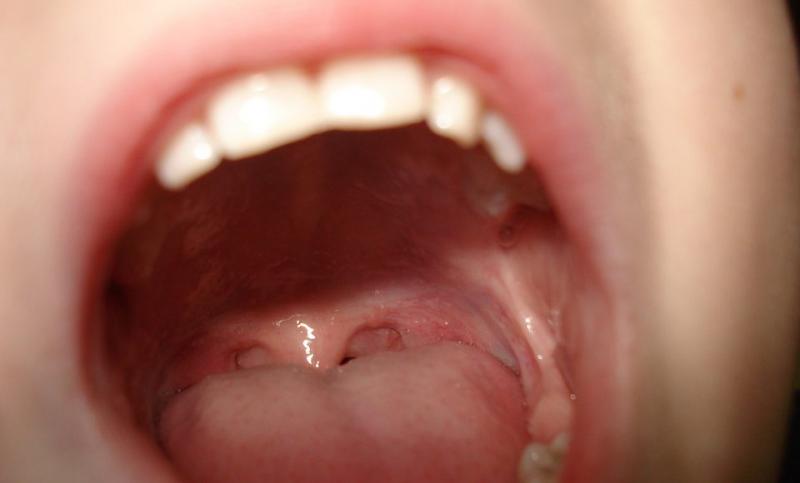

Damakta yara, ağız içinde yaygın olarak karşılaşılan ve çeşitli nedenlere bağlı olarak gelişebilen bir durumdur. Bu makalede, damakta yara belirtileri, olası nedenleri ve tedavi yöntemleri üzerinde durulacaktır. 1. Damakta Yara Nedir?Damakta yara, genellikle ağrı, rahatsızlık ve iltihaplanma ile kendini gösteren bir durumdur. Yara, damak zarı üzerinde, genellikle beyaz veya kırmızı renkte, yaralı bir alan olarak gözlemlenir. 2. Damakta Yara BelirtileriDamakta yaraların belirtileri kişiden kişiye değişiklik gösterebilir, ancak en yaygın belirtiler şunlardır: